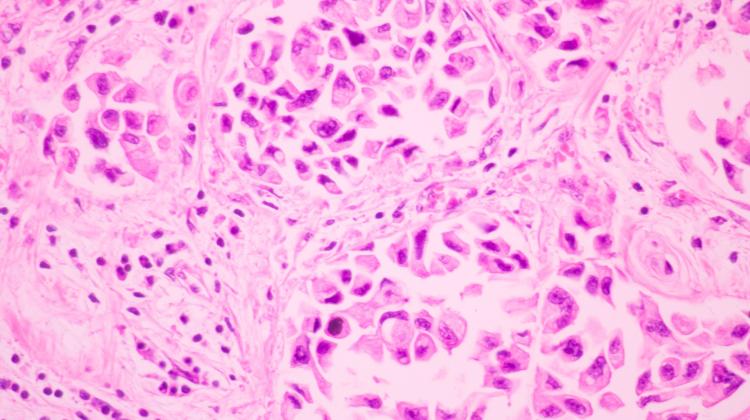

Процесс накопления генетических мутаций, приводящих к развитию рака молочной железы и яичников, можно лучше понять благодаря модели Аврами-Добжинского, разработанной польскими учеными. Физики использовали аналогию с формированием кристаллов. Анализ рисков может значительно ускорить диагностику.

Чтобы применить биофизическую модель образования рака на практике, ученые использовали аналогию процесса фазового перехода в физике с процессом трансформации рака в клетках. Они перевели физическую концепцию зарождения и роста кристаллов на язык биологии. Они использовали модифицированное уравнение Аврами для определения вероятности рака. По мнению команды, модель имеет важное клиническое значение. «Многоточечная модель канцерогенеза предполагает, что рак возникает в результате последовательного накопления в клетках множества генетических мутаций, что приводит к нарушению нормальных клеточных функций и развитию злокачественных опухолей. Когда количество онкогенных мутаций превышает определенное количество критическое значение, раковая трансформация клетки происходит как быстрый нелинейный процесс, аналогичный явлению физического фазового перехода", - поясняется на сайте Варшавского технологического университета. Исследования координируют ученые кафедры физики сложных систем физического факультета Варшавского технологического университета. По данным университета, над моделью работали, в частности, Кшиштоф В. Форнальский с физического факультета Варшавского технологического университета и Национального центра ядерных исследований. Статья об использовании модели опубликована в Международном журнале молекулярных наук. Его соавторы: Анна Завадская и Михал Микула из Национального научно-исследовательского института онкологии. Мария Склодовская-Кюри, Беата Бжозовская и Адрианна Тартас с физического факультета Варшавского университета, Анна Матьянка с физического факультета Варшавского технологического университета и Иоанна Рещиньская с кафедры нейроонкологии Института экспериментальных и Клиническая медицина. Мирослав Моссаковский Польской академии наук. Исследователи проанализировали данные о раке молочной железы и яичников среди пациентов Национального института онкологии. Мария Склодовская-Кюри в Варшаве. Оказалось, что у пациентов с наследственными мутациями гена BRCA1/BRCA2 рак можно диагностировать примерно на два года раньше, чем у остальных людей. Ученые намерены продолжить исследования, предполагающие, что канцерогенные процессы протекают по фрактальной динамике. Медицинская физика – новая область, интенсивно развивающаяся во многих центрах мира, в том числе на физическом факультете Варшавского политехнического университета, где проводится серия семинаров «Физика рака». Наука в Польше цвет/бар/